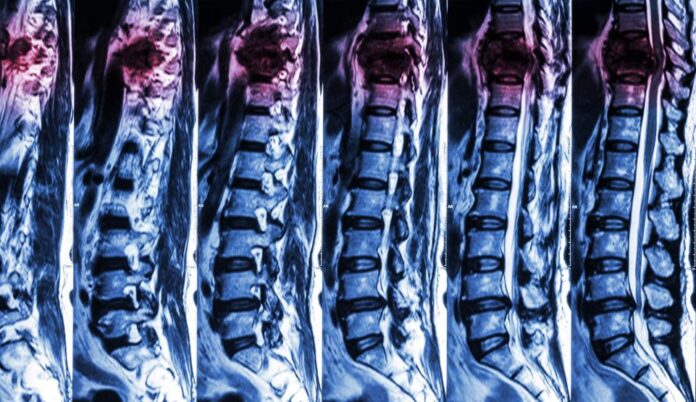

Secționarea măduvei spinării este una dintre cele mai grave daune pe care o poate suferi corpul uman și, în funcție de locul secționării, poate genera o paralizie totală (brațe + picioare) sau una parțială (a picioarelor).

„Nouă persoane care au suferit de paralizie severă sau completă ca urmare a leziunilor măduvei spinării și-au recăpătat într-o anumită măsură capacitatea de a merge, potrivit unui studiu al cercetătorilor de la grupul de cercetare elvețian NeuroRestore. Astfel, toți voluntarii au arătat semne imediate de îmbunătățire și au continuat să progreseze chiar și după cinci luni.

Oamenii de știință au identificat celulele nervoase responsabile pentru a ajuta persoanele paralizate să meargă din nou, deschizând posibilitatea unor terapii țintite de care ar putea beneficia persoane cu leziuni ale măduvei spinării.”, scrie biziday.ro